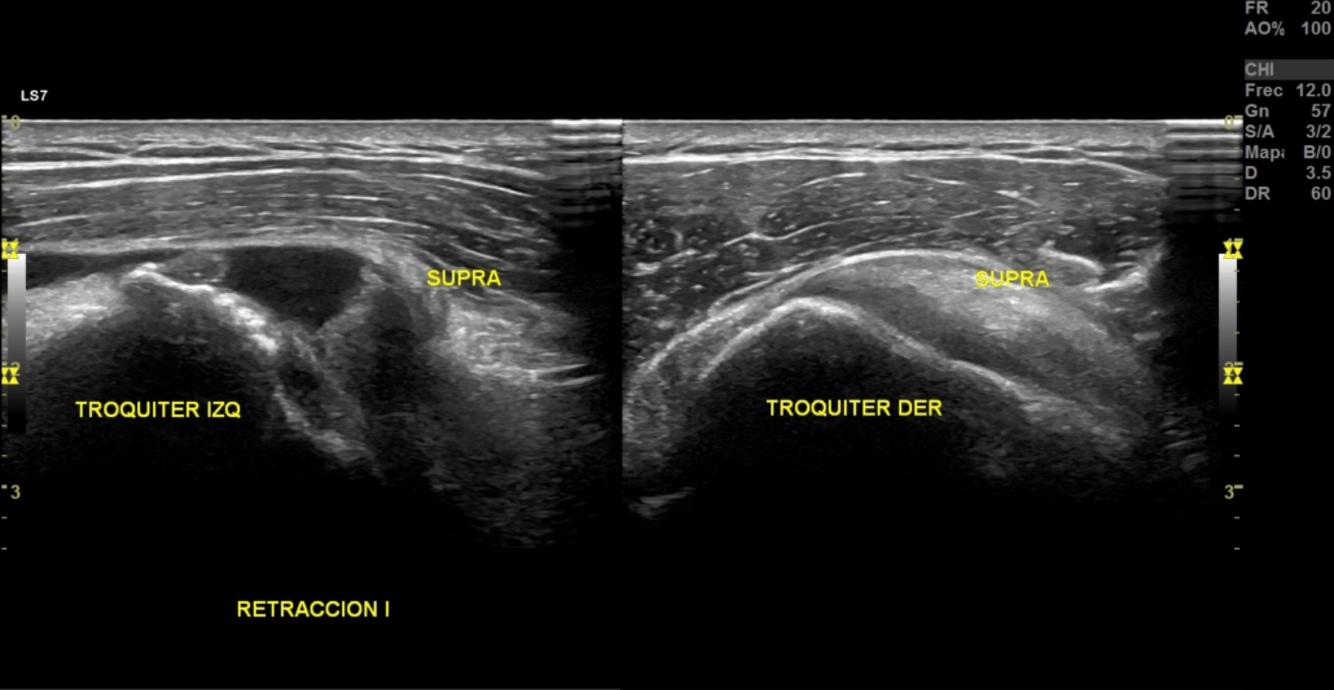

90% sensibilidad y especificidad

Diagnóstica rotura y pinzamiento

US

A

Normal

Deltoides

Bursa

Supraespinoso

Cartilago

Humero

Rotura tendon supraespinosos

Rotura tendon supraespinoso